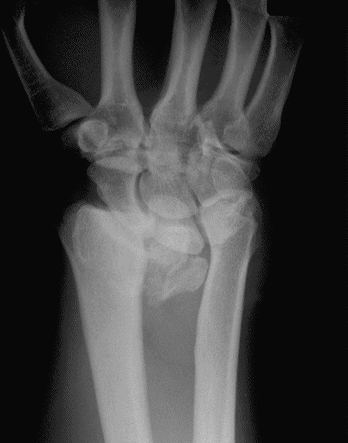

Case 4 Preop